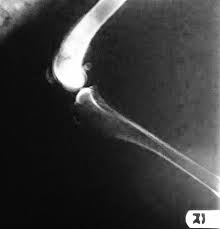

How Long Will A Dog Live With Bone Cancer Without Treatment / Bone Cancer Osteosarcoma In Dogs Canna Pet / Other types of bone cancer include chondrosarcoma, fibrosarcoma, and hemangiosarcoma.. Other types of bone cancer include chondrosarcoma, fibrosarcoma, and hemangiosarcoma. Life expectancy for dogs with bone cancer even with aggressive treatment options such as amputation and chemotherapy, your dog's life expectancy is only about a year. Once a dog has been diagnosed with osteosarcoma, their average life expectancy without any treatment is approximately two months. The exact mechanism of how cancer cells metastasize to the bones isn't fully known. However, due to the intense pain at the site of the bone tumor, the dog will probably be euthanized prior to this period of time.

Or a small lump on the leg that becomes tender to the touch. With treatment, survival time is about 12 months. In the next blog we will talk about other conventional treatment options, including radiosurgery and palliative radiation. A type of bone cancer called osteosarcoma is the most common type of primary bone cancer in dogs, accounting for over 95% of all bone tumors. Bone marrow cancer average cost. For them, surgery is not an option, and the prognosis is not very good. Without therapy average survival time is approximately two months. This is primarily determined by the discomfort associated with the primary tumour. Chemotherapy is a common treatment to help slow the spread of the disease—as left untreated, the average life expectancy for dogs after diagnosis under three months. Following diagnosis of osteosarcoma in dogs, life expectancy can be summarised as follows: Dogs with very severe arthritis and some neurological conditions may not be able to walk well after an amputation. More than 90 percent of affected dogs succumb to the disease within two years—despite amputation of the affected leg, followed by chemotherapy to stop or slow the cancer's spread. Other types of bone cancer include chondrosarcoma, fibrosarcoma, and hemangiosarcoma.

Bone Cancer Osteosarcoma In Dogs Canna Pet from g77v3827gg2notadhhw9pew7-wpengine.netdna-ssl.com Median survival times for osa cases with amputation and no other treatment is about four to five months. Or a dramatic, sudden fracture. This may be shorter or longer depending on when they are diagnosed. A type of bone cancer called osteosarcoma is the most common type of primary bone cancer in dogs, accounting for over 95% of all bone tumors. This is primarily determined by the discomfort associated with the primary tumour. This is a malignant tumor that is said to be slow progressing. Or a small lump on the leg that becomes tender to the touch. Dogs at ages between 7 and 10 years have a significantly higher survival rate than younger and older dogs with most bone cancers, including osa and csa.

3 common types of bone cancer: With amputation alone, most dogs only live four or five months. Following diagnosis of osteosarcoma in dogs, life expectancy can be summarised as follows: This is a malignant tumor that is said to be slow progressing. With other bone cancers, such as axial. And others will continue to live comfortably for months on end. Median survival times for osa cases with amputation and no other treatment is about four to five months. In the next blog we will talk about other conventional treatment options, including radiosurgery and palliative radiation. The standard of care is surgery (amputation of limb sparing surgery) with adjuvant chemotherapy. Prognosis for osteosarcoma in a dog the average life expectancy of dogs with appendicular osteosarcoma that don't receive treatment is 2 to 4 months. However, due to the intense pain at the site of the bone tumor, the dog will probably be euthanized prior to this period of time. According to scientists, the average lifespan of those dogs is about 2 to 3 months. This article is focused (in broad terms) on chondrosarcoma in dogs.